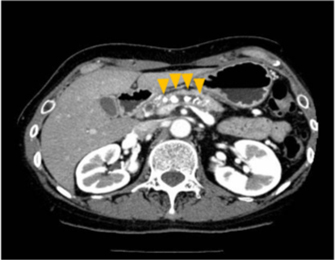

【慢性膵炎のCT画像】

太くなった膵管の中に白い膵石(矢頭)が複数認められる